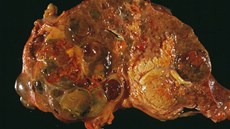

Rakovinu jater dělíme na primární a sekundární neboli metastatickou. Primární nádory vznikají přímo v jaterní tkáni a nejčastěji jde o hepatocelulární karcinom a cholangiokarcinom. Na rozdíl od metastatických nádorů, které se do jater šíří z jiných orgánů, je primární rakovina jater nemoc, která v játrech vzniká sama o sobě, často na podkladě dlouhodobého poškození.

Primární rakovina jater se nejčastěji vyskytuje u lidí, kteří mají dlouhodobě nemocná játra. Patří sem především pacienti s cirhózou, bez ohledu na to, zda je způsobena alkoholem, hepatitidou B či C, nebo jinými chronickými záněty a poruchami. Významným rizikem je také nealkoholové tukové onemocnění jater, dnes velmi rozšířené kvůli obezitě, sedavému stylu života a metabolickým poruchám.